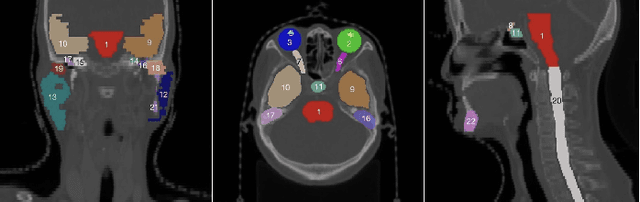

Abstract:Accurate segmentation of organs at risk in the head and neck is essential for radiation therapy, yet deep learning models often fail on small, complexly shaped organs. While hybrid architectures that combine different models show promise, they typically just concatenate features without exploiting the unique strengths of each component. This results in functional overlap and limited segmentation accuracy. To address these issues, we propose a high uncertainty region-guided multi-architecture collaborative learning (HUR-MACL) model for multi-organ segmentation in the head and neck. This model adaptively identifies high uncertainty regions using a convolutional neural network, and for these regions, Vision Mamba as well as Deformable CNN are utilized to jointly improve their segmentation accuracy. Additionally, a heterogeneous feature distillation loss was proposed to promote collaborative learning between the two architectures in high uncertainty regions to further enhance performance. Our method achieves SOTA results on two public datasets and one private dataset.

Abstract:The task of labeling multiple organs for segmentation is a complex and time-consuming process, resulting in a scarcity of comprehensively labeled multi-organ datasets while the emergence of numerous partially labeled datasets. Current methods are inadequate in effectively utilizing the supervised information available from these datasets, thereby impeding the progress in improving the segmentation accuracy. This paper proposes a two-stage multi-organ segmentation method based on mutual learning, aiming to improve multi-organ segmentation performance by complementing information among partially labeled datasets. In the first stage, each partial-organ segmentation model utilizes the non-overlapping organ labels from different datasets and the distinct organ features extracted by different models, introducing additional mutual difference learning to generate higher quality pseudo labels for unlabeled organs. In the second stage, each full-organ segmentation model is supervised by fully labeled datasets with pseudo labels and leverages true labels from other datasets, while dynamically sharing accurate features across different models, introducing additional mutual similarity learning to enhance multi-organ segmentation performance. Extensive experiments were conducted on nine datasets that included the head and neck, chest, abdomen, and pelvis. The results indicate that our method has achieved SOTA performance in segmentation tasks that rely on partial labels, and the ablation studies have thoroughly confirmed the efficacy of the mutual learning mechanism.

Abstract:Accurate segmentation of multiple organs of the head, neck, chest, and abdomen from medical images is an essential step in computer-aided diagnosis, surgical navigation, and radiation therapy. In the past few years, with a data-driven feature extraction approach and end-to-end training, automatic deep learning-based multi-organ segmentation method has far outperformed traditional methods and become a new research topic. This review systematically summarizes the latest research in this field. For the first time, from the perspective of full and imperfect annotation, we comprehensively compile 161 studies on deep learning-based multi-organ segmentation in multiple regions such as the head and neck, chest, and abdomen, containing a total of 214 related references. The method based on full annotation summarizes the existing methods from four aspects: network architecture, network dimension, network dedicated modules, and network loss function. The method based on imperfect annotation summarizes the existing methods from two aspects: weak annotation-based methods and semi annotation-based methods. We also summarize frequently used datasets for multi-organ segmentation and discuss new challenges and new research trends in this field.